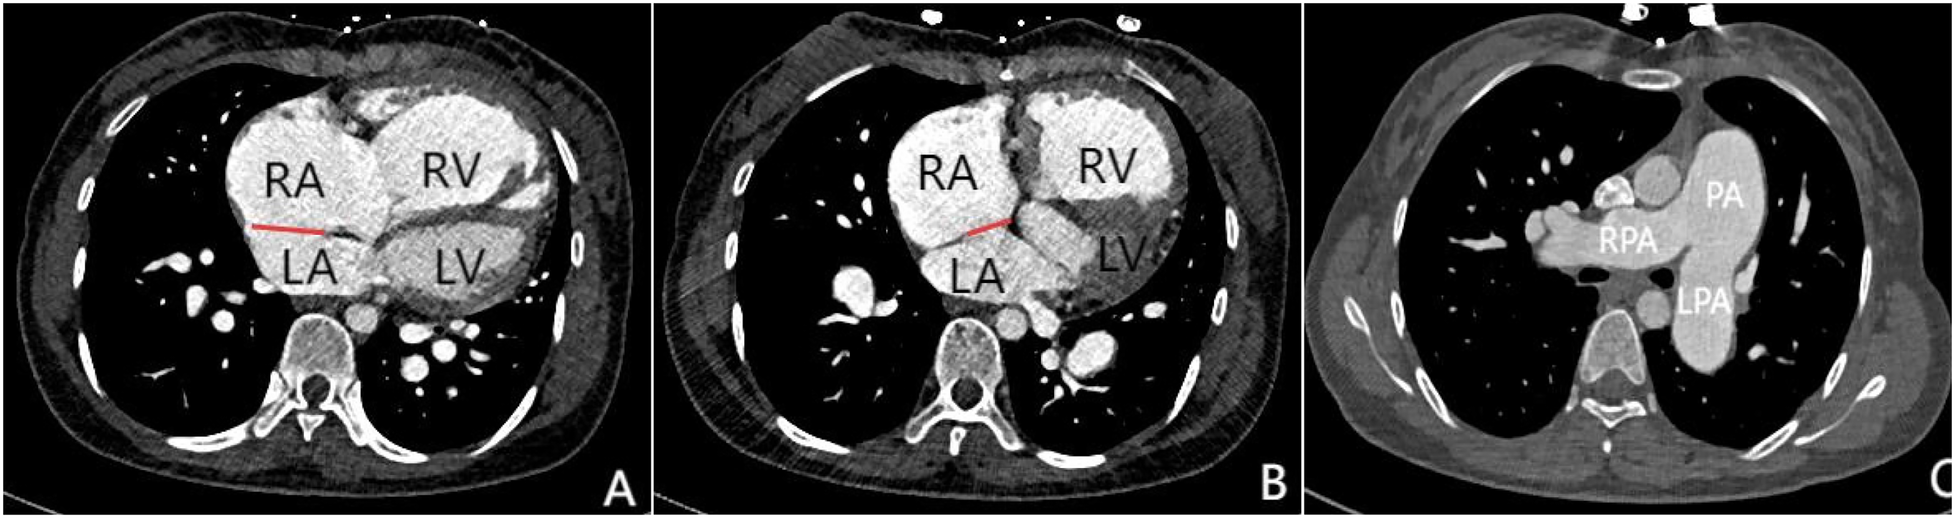

Transthoracic echocardiography (TTE) revealed an atrial septal defect (ASD) with a 3 cm opening (Figure 1), along with partial anomalous pulmonary venous drainage. Pulmonary artery systolic pressure (PASP) was 147 mmHg by measuring the tricuspid regurgitation spectrum using continuous Doppler., and severe tricuspid regurgitation, the inner diameter of the main pulmonary artery widened slightly, about 3 cm, left ventricular ejection fraction(LVEF) 69% were noted. Coronary CT angiography (CTA) confirmed these abnormalities and revealed a multi-fenestrated ASD (measuring 2.8 × 3.1 cm and 1.8 × 1.9 cm), the dorsal and basal segmental branches of the right inferior pulmonary vein drain abnormally into the inferior vena cava at its junction with the left atrium. Chest and abdominal CT angiography (CTA) further confirmed the IVC anomaly draining into the left atrium (Figures 2, 3). Right heart catheterization confirmed severe pulmonary hypertension, revealing a pulmonary artery pressure of 117/40 mmHg (mean 60 mmHg). While a full set of hemodynamic measurements including cardiac output was not obtained during the procedure, the documented pulmonary artery pressures were sufficient to establish the diagnosis of severe PAH and guide the initial therapeutic strategy (Figure 4).

Figure 2

Panels (A–C) are all axial images from contrast-enhanced CT scans. Panels (A and B) demonstrate atrial septal defects at different locations (indicated by the red lines), measuring 3.1 cm and 1.8 cm in size respectively. Simultaneously, significant enlargement of the right atrium and right ventricle can be observed. Panel (C) shows marked dilation of the pulmonary trunk and both left and right pulmonary arteries, which is consistent with signs of pulmonary hypertension.